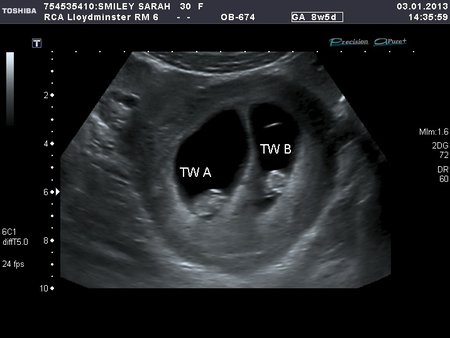

Gestational age is historically derived on the basis of the first day of the last menstrual period LMP. This is called the dating scan. Does screening for Down's syndrome happen at the dating scan. You might be offered another test to find out for certain if there is a problem. For BPD the outer—outer diameter was measured perpendicular to the midline and for HC an autobus was drawn around the outline of the skull. Your choice will be respected if you decide not to have the scans, and your antenatal care will continue as normal. National Collaborating Centre for Women's and Children's Health NCCWCH. American Institute for Ultrasound in Medicine. How prime are ultrasounds in calculating gestational age. An example of this dating is shown in Figure 53-3. If you prefer, you can have a.

The objectives of this study were, first, to develop charts for ultrasound dating of pregnancy based on crown—rump length and biparietal diameter and, second, to derive reference curves for normal fetal growth based on biparietal diameter, head circumference, transverse cerebellar diameter, abdominal circumference and femur length from 10 weeks of gestational age onwards. The ultrasound is usually done through your belly, though sometimes a offers better views. As soon as data from the LMP, the first accurate examination, or both ultrasound obtained, the gestational age and the EDD should be determined, discussed with the patient, and documented clearly in the medical record. what is a dating ultrasound

One of the most important aspects of obstetrical care is to date, as precisely as possible, the beginning of pregnancy so that the estimated time of arrival ETA can be calculated sometimes referred to as the estimated date of confinement — EDC. And yet, even with all of the available technology, one of the puzzles of modern obstetrics, is that the obstetrician has not yet learned how to accurately date the beginning of a pregnancy. Pregnancy can be measured in two different ways. The most common and most often used in clinical obstetrics is the measurement of the gestational age of the pregnancy. The gestational age of the pregnancy is measured from the first day of the last menstrual period. In this way of dating the pregnancy, the pregnancy is 40 weeks in duration on average instead of the actual 38 weeks. In other words, it dates the pregnancy, on average, two weeks longer than it is. The other way of measuring the dates of the pregnancy is to measure the fetal age. The fetal age of the pregnancy is measured from the time of conception or the estimated time of conception ETC. When measuring the pregnancy in this fashion, it will be 38 weeks long or two weeks shorter than the gestational age dates. The fetal age, of course, is the actual age of the pregnancy. Historically, the obstetrician has focused on the first day of the last menstrual period for two reasons. First of all, the menstrual flow itself is a fairly dramatic symptom which the woman can be expected to remember. In addition, it is easy to teach her to record the first day of the last menstrual period so that when that information is elicited by the physician, at a later time, it is available. However, in the midst of all of this, the obstetrician and many women have missed the point that the cervical mucus discharge is very much a flow in the same fashion as the menstrual flow. In some countries, they refer to menstruation as the red flow and the mucus discharge as the white flow. Unfortunately, modern obstetrics has paid little attention to the white flow. Therefore, one can date the pregnancy according to its true date or true beginning or in fetal age terms. This is measured by evaluating the acts of intercourse that occur during the time of fertility and establishing an estimated time of conception through this approach. We have studied 173 patients in a consecutive fashion who have been charting the CrMS at the time of conception. The ETC and the ETA were calculated. In this group of patients, early ultrasound dating of the pregnancy was also obtained. In Table 53-3, the results of that evaluation are shown. An accurate date for the beginning of pregnancy can be established with the use of the CrMS. This correlates well with the ultrasound dates and the estimated due date or ETA. The CrMS dates were highly accurate with the two being within 10 days of each other in 100 percent of the cases. An example of this dating is shown in Figure 53-3. Here, a pregnancy occurring in a longer cycle where the Peak Day occurred on Day 26 of the cycle is shown. If this pregnancy is calculated in the traditional fashion, there will be a 12-day discrepancy between the dates as customarily calculated from the last menstrual period and the actual date of the pregnancy which is calculated from the Peak Day. The Peak Day, of course, will be much more accurate.